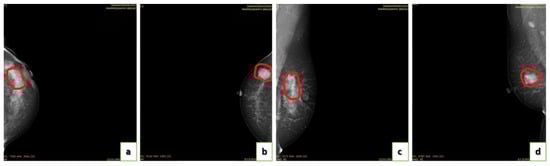

4.2. Annotation of Images

- Image labeling.

- Image validation by a committee of radiologists.